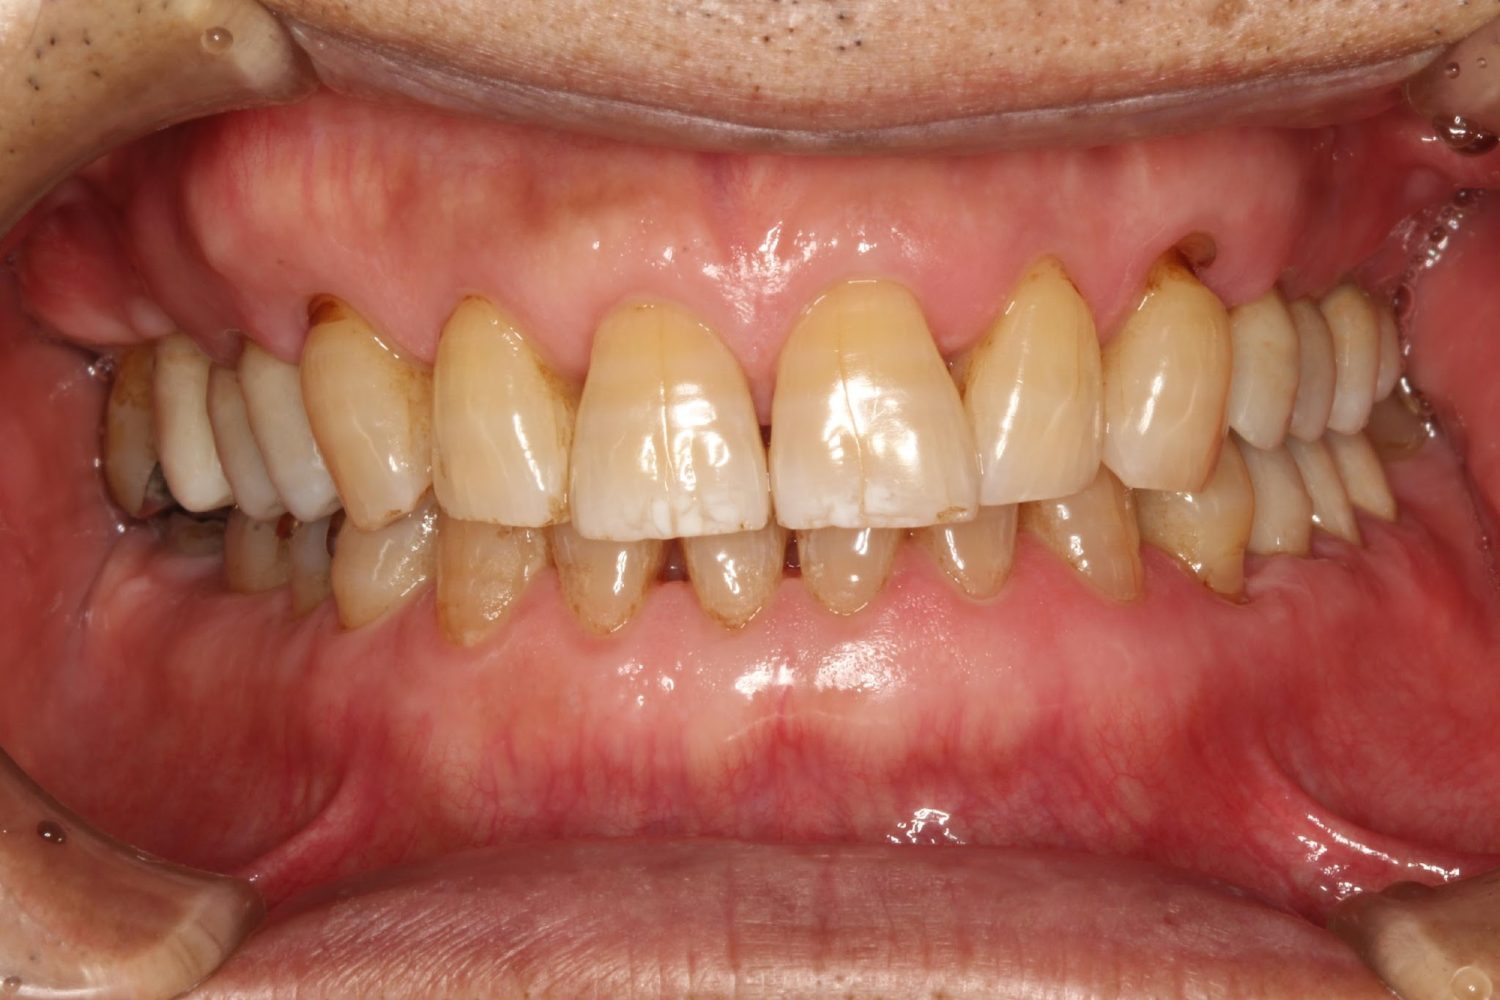

インプラント治療の症例紹介④

Before

After

主訴

義歯による疼痛

治療内容

下顎舌側に骨隆起があり義歯困難な状態。保存不可能な歯の抜歯を行い、インプラントを埋入し咬合再構成を行った。

治療費

2,851,200円(税込)

治療期間

29ヶ月

通院回数

26回

想定されたリスク

※咬合力の強い方なので、予防的にマウスピースの装着が必要。インプラント周囲炎の恐れがありました。

歯の欠損の対合歯の挺出等を修正し咬合平面を揃え咬合再構成を行った症例。